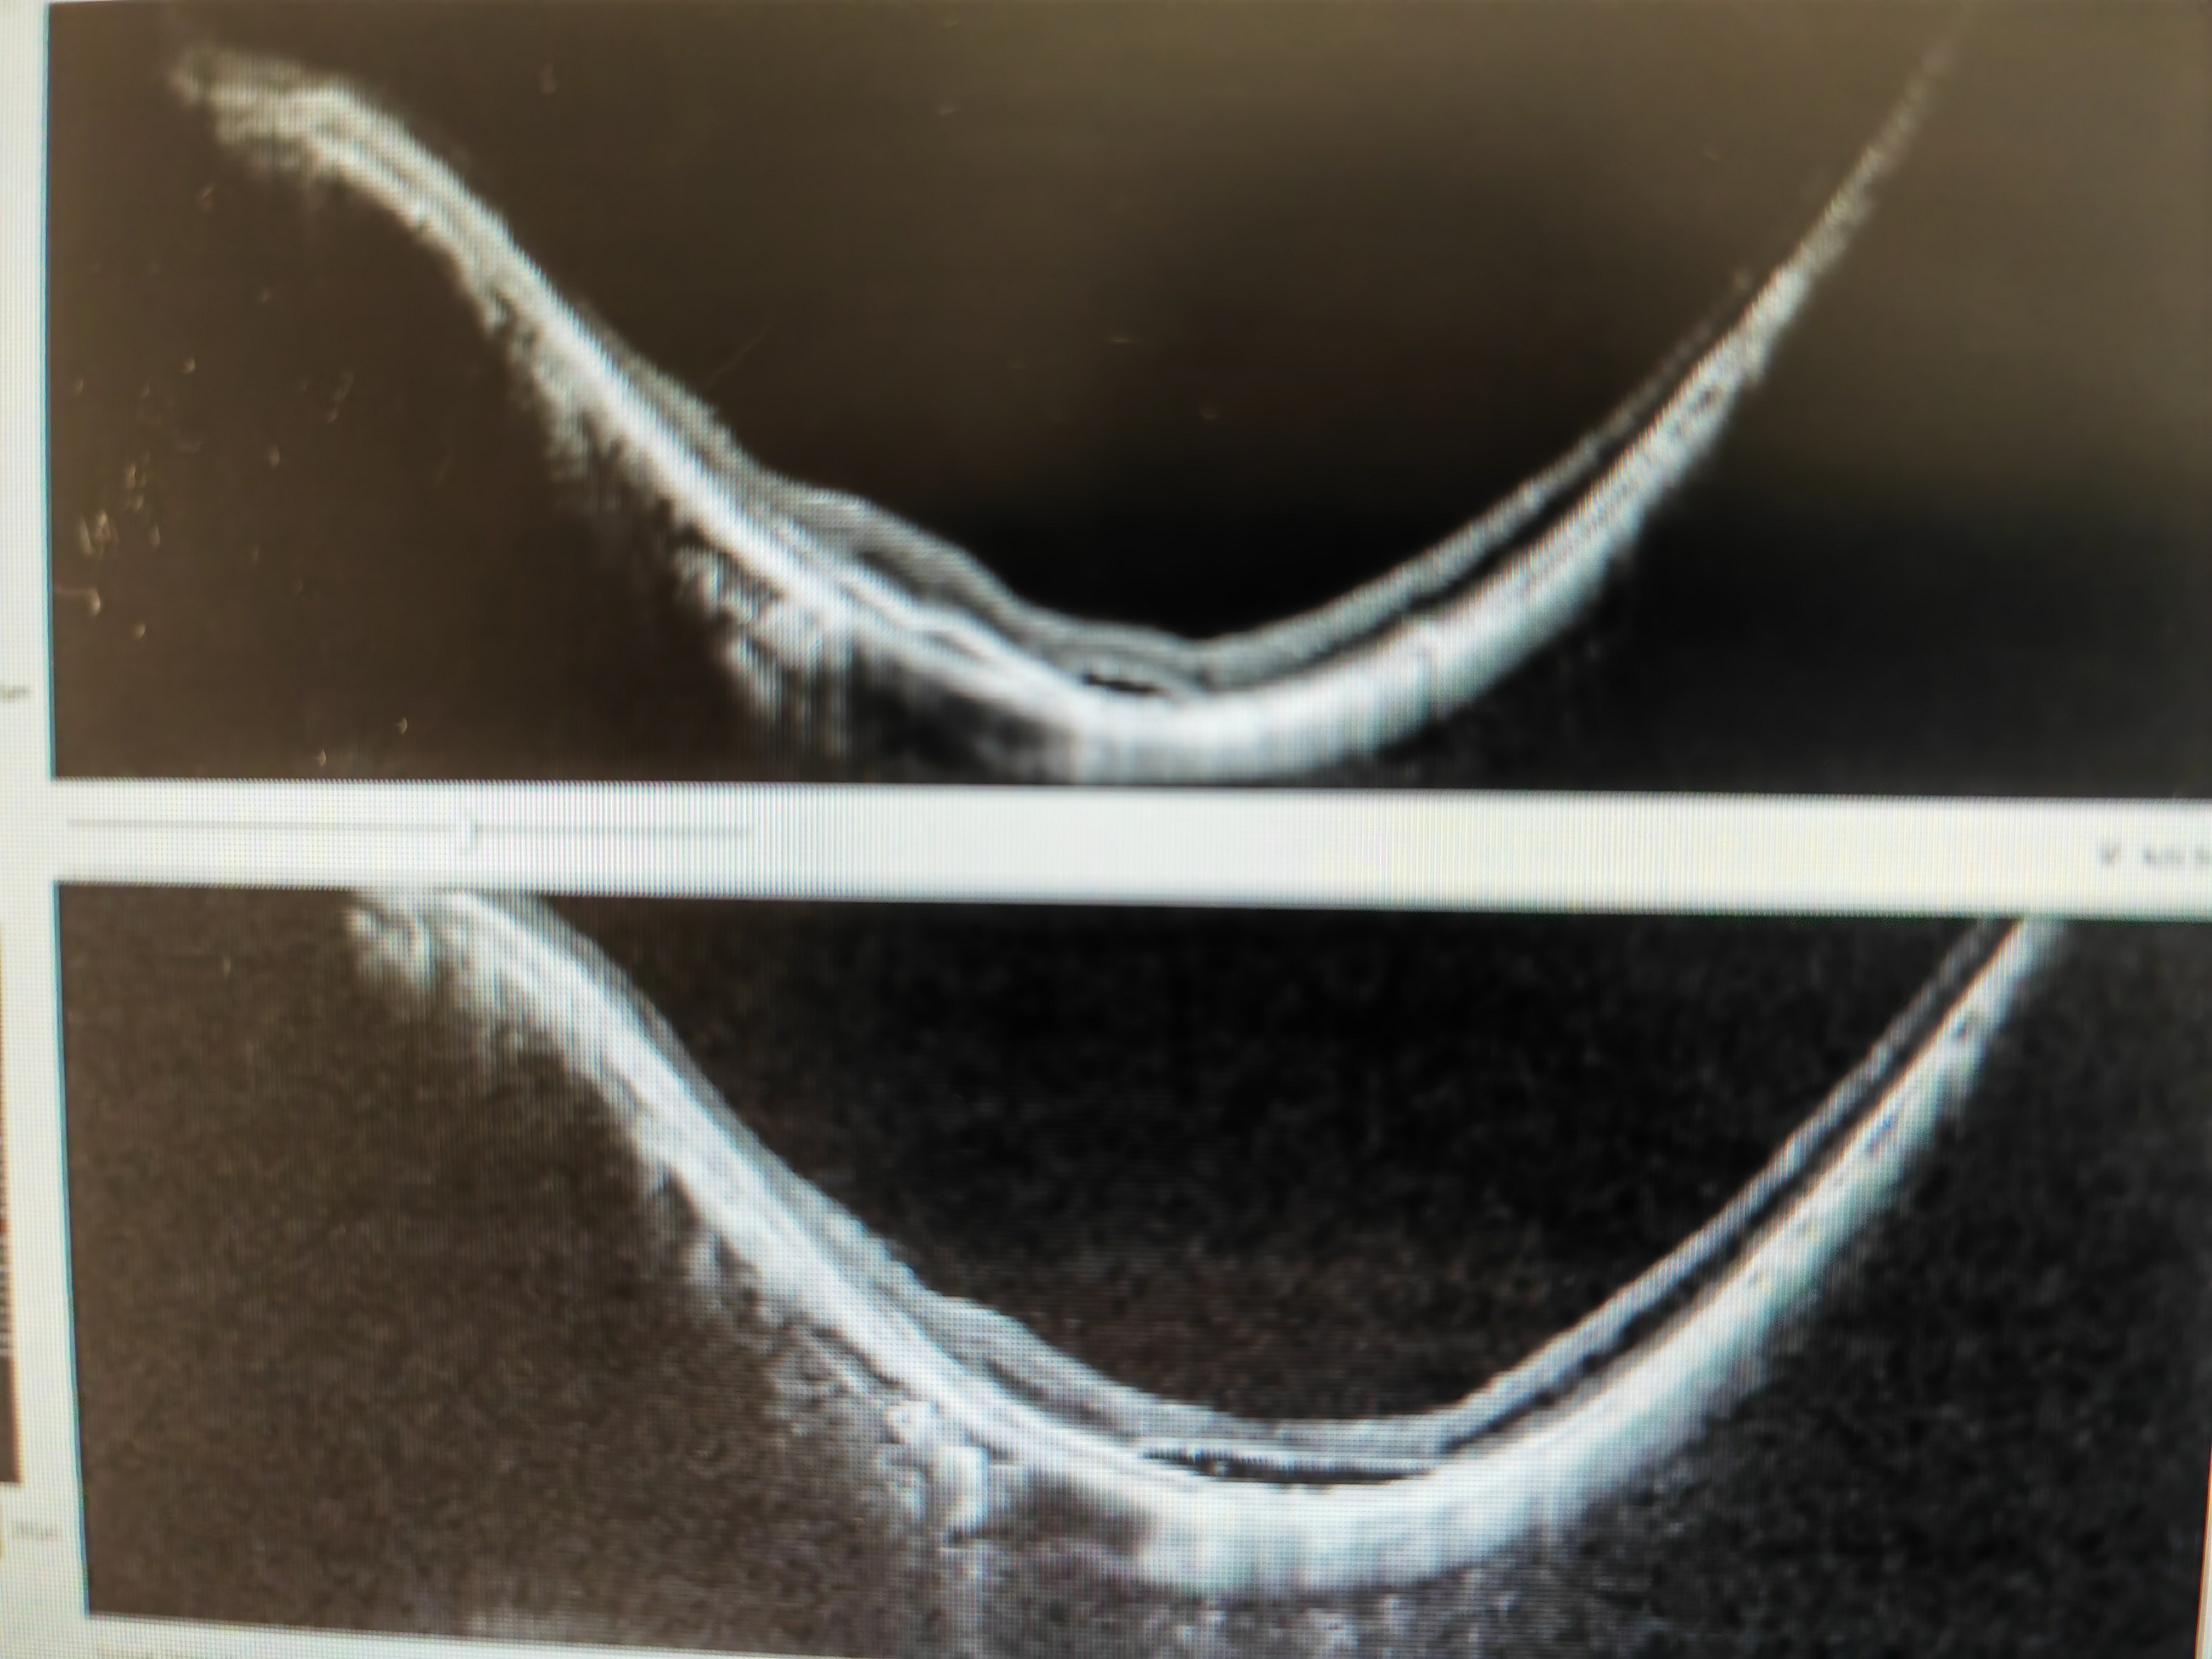

隨著年齡增長(zhǎng),高度近視眼可發(fā)生嚴(yán)重的黃斑劈裂,甚至視網(wǎng)膜脫離,視力突然下降。常規(guī)的手術(shù)方法是玻璃體切割手術(shù)聯(lián)合內(nèi)界膜剝除術(shù)。該手術(shù)的成功率在70%,有30%的失敗病例會(huì)發(fā)生黃斑裂孔,視力進(jìn)一步下降。有病人甚至需要硅油注入以及硅油取出兩次手術(shù)。我們近5年來(lái)一直采用SHIMADA教授以及趙培泉教授設(shè)計(jì)的保留中心凹內(nèi)界膜剝除術(shù),該方法成功率為90%,是治療嚴(yán)重黃斑劈裂安全有效的手術(shù)方式?;颊咄ㄟ^半年左右的恢復(fù),黃斑劈裂將逐漸修復(fù),視力改善。病例1病例2這一手術(shù)革新可以讓更多的高度近視黃斑劈裂患者受益。